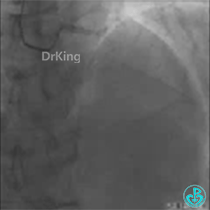

资料:患者女,66岁。

主诉:间断胸闷气短3年,加重4天。

病史:患者3年前活动或感冒后出现胸闷气短症状,一直未予重视;4天前胸闷、气短加重,伴双下肢轻度水肿。

既往史:无。

手术史:1月前来我院住院,对LCX闭塞血管进行开通,植入支架2枚。

查体:T 36.5℃,P 70次/分,BP 110/66mmHg。双肺未闻及啰音。

病变小结

1. 该患者冠脉分布为右冠优势型;

2. LAD近段和D1开口为分叉病变;

3. D1开口与LAD主支血管成角较大;

4. 几乎可以预测D1血管导丝进入可能会出现困难。